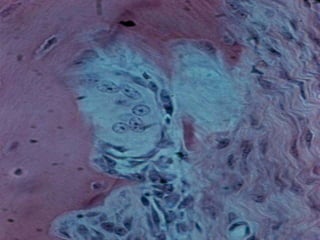

The odontoclasts are easily recognized , with light

microscope , in clusters rather than singly and appear

occupying hollowed-out shallow depressions known

Howship's lacunae .

An odontoclast is a large cell that is characterized by

multiple nuclei and a cytoplasm with a homogeneous,

"foamy" appearance. This appearance is due to a high

concentration of vesicles and vacuoles. At a site of

active dentin resorption, the odontoclast forms a

specialized cell membrane, the "ruffled border“ ( brush

border ) , which faces the surface of the dentin tissue.

The ruffled border facilitates removal of the dentin

matrix. The ruffled border increases surface area

interface for dentin resorption. The mineral portion of

the matrix (called hydroxyapatite) includes calcium and

phosphate ions. These ions are absorbed into small

vesicles which move across the cell and eventually are

released into the extracellular fluid, thus increasing

levels of the ions in the blood.